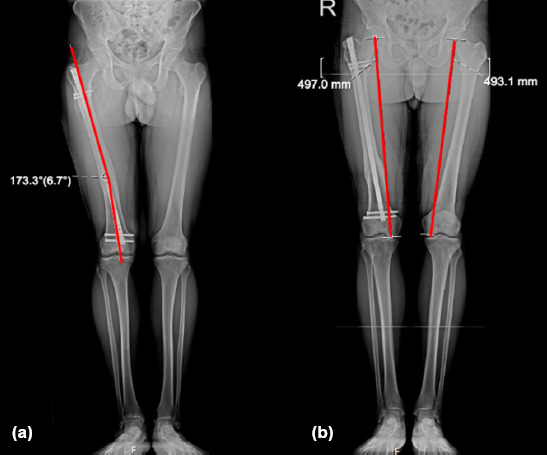

Methods: A retrospective cohort study was conducted involving 54 adults treated with closed static-locked IMN for diaphyseal femur fractures between 2014 and 2019. Rotational alignment was assessed using computed tomography (CT)-measured femoral anteversion (FAV) differences, with a threshold of ≥15° defined as malalignment. Multivariate logistic regression was employed to examine associations with fracture pattern, nail entry site, surgical timing (day vs. night), and coronal alignment. Functional outcomes were assessed using the WOMAC (Western Ontario and McMaster Universities Osteoarthritis Index) knee, Harris hip, Lower Extremity Functional Scale, and Kujala patellofemoral scores. Receiver operating characteristic (ROC) analysis was used to determine optimal FAV thresholds.

Results: Rotational malalignment (≥15° FAV difference) was observed in 33.3% of cases, with 94.4% involving internal rotation. Multivariate analysis identified no independent predictors among the following factors: fracture location (proximal 44.4% vs. middle 29.2%, p=0.625), AO classification (Type A 34.3% vs. Type C 33.3%, p=0.914), nail entry site (lateral trochanteric 40% vs. piriformis 16.6%, *p*=0.574), and surgical timing (night 26.1% vs. day 38.7%, p=0.228). Patients with malalignment demonstrated significantly poorer functional outcomes, as evidenced by higher WOMAC knee scores (12.7+-4.8 vs. 6.4+-4.8, p<0.001). ROC curve analysis identified 13.5° as the optimal FAV threshold (area under the curve, AUC: 0.78), although the 15° cutoff maintained strong clinical utility with a specificity of 83%.